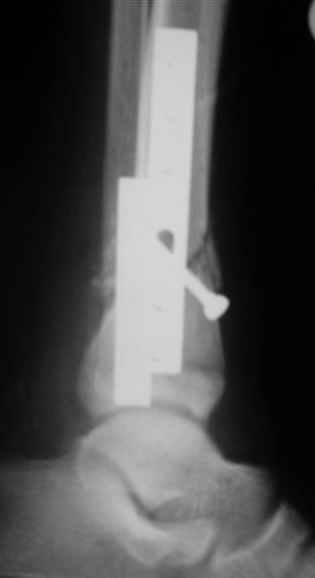

В аттачтах №№ 1 и 2 - примеры, когда 2 кольца не позволили послеоперационно

исправить смещение фрагментов большеберцовой (по ширине и вальгусное).

А казалось бы (#2) - поиграй на штангах и все влетит.

Оперировал не я

1

1a